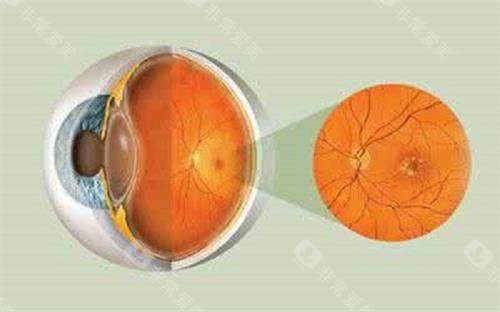

眼底病与眼外伤专科:显微手术的"艺术"

余锦强医师是玻璃体视网膜疾病领域的显要,尤其擅长复杂性视网膜脱离、糖尿病视网膜病变的小创口玻切手术,手术精细度高,视功能重建改善显著。华远锋副高医师则在眼外伤急诊处理方面技术娴熟,能够及时救治眼球破裂伤等急症,更大限度保留患者眼球结构和功能。